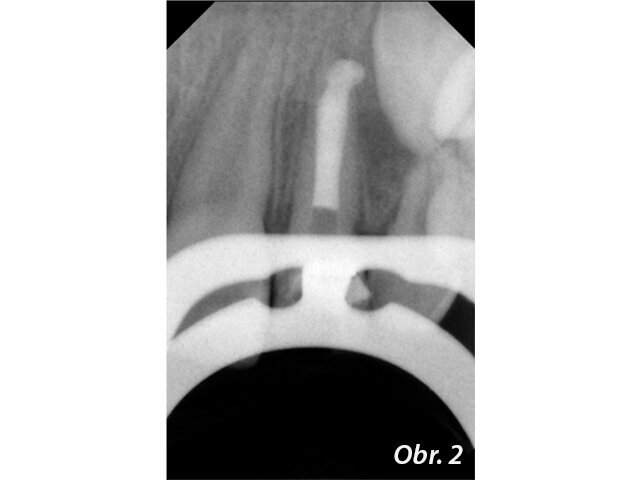

Dodržení pravidla, že během endodontického ošetření má být ošetřovaný zub izolován kofferdamem, je u zubů s nedokončeným vývojem kořene často komplikováno neúplným prořezáním zubu. Chybí podsekřivý prostor pro retenci spony. V některých případech může pomoci dočasná adhezivní fixace spony na ošetřovaném zubu. Jindy – především u řezáků, však ani takováto fixace spony není možná. Lze pak například sponu nasadit na některý z laterálních zubů a na ošetřovaném řezáku zajistit pouze retenci pro kofferdamovou fólii (viz obr. 13 a 14).